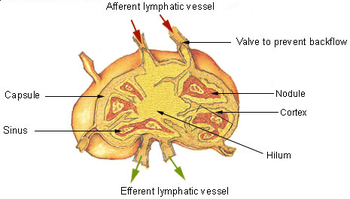

Lymph nodes are kidney or oval shaped and range in size from a few millimeters to about 1–2 cm long.[4] Each lymph node is surrounded by a fibrous capsule, and inside the lymph node the fibrous capsule extends to form trabeculae. The substance of the lymph node is divided into the outer cortex and the inner medulla. The cortex is continuous around the medulla except at the hilum, where the medulla comes in direct contact with the hilum.[4]

Lymph enters the convex side of the lymph node through multiple afferent lymphatic vessels, to flow through the sinuses. A lymph sinus which includes the subcapsular sinus, is a channel within the node, lined by endothelial cells along with fibroblastic reticular cells and this allows for the smooth flow of lymph through them.The endothelium of the subcapsular sinus is continuous with that of the afferent lymph vessel and is also with that of the similar sinuses flanking the trabeculae and within the cortex. All of these sinuses drain the filtered lymphatic fluid into the medullary sinuses, from where the lymph flows into the efferent lymph vessels to exit the node at the hilum on the concave side.[4] These vessels are smaller and don't allow the passage of the macrophages so that they remain contained to function within the lymph node. In the course of the lymph, lymphocytes may be activated as part of the adaptive immune response.

The lymph node capsule is composed of dense irregular connective tissue with some plain muscle fibers, and from its internal surface are given off a number of membranous processes or trabeculae, consisting, in humans, of connective tissue, with a small admixture of plain muscle fibers; but in many of the lower animals composed almost entirely of involuntary muscle. They pass inward, radiating toward the center of the gland, for about one-third or one-fourth of the space between the circumference and the center of the node. In some animals they are sufficiently well-marked to divide the peripheral or cortical portion of the gland into a number of compartments (follicles), but in humans this arrangement is not obvious. The larger trabeculae springing from the capsule break up into finer bands, and these interlace to form a mesh-work in the central or medullary portion of the gland. In these spaces formed by the interlacing trabeculae is contained the proper gland substance or lymphoid tissue. The gland pulp does not, however, completely fill the spaces, but leaves, between its outer margin and the enclosing trabeculae, a channel or space of uniform width throughout. This is termed the subcapsular sinus (lymph path or lymph sinus). Running across it are a number of finer trabeculæ of reticular connective tissue, the fibers of which are, for the most part, covered by ramifying cells.

Subcapsular sinus

The subcapsular sinus (lymph path, lymph sinus, marginal sinus) is the space between the capsule and the cortex which allows the free movement of lymphatic fluid and so contains a sparsity of lymphocytes.[4] It is continuous with the similar lymph sinuses that flank the trabeculae.[4]

Cortex

The cortex of the lymph node is the peripheral portion underneath the capsule and the subcapsular sinus.[6] The subcapsular sinus drains to trabecular sinuses, and then the lymph flows into the medullary sinuses.

Medulla

The medulla contains large blood vessels, sinuses and medullary cords that contain antibody-secreting plasma cells.

The medullary cords are cords of lymphatic tissue, and include plasma cells, macrophages, and B cells. The medullary sinuses (or sinusoids) are vessel-like spaces separating the medullary cords. Lymph flows into the medullary sinuses from cortical sinuses, and into efferent lymphatic vessels. Medullary sinuses contain histiocytes (immobile macrophages) and reticular cells.

Lymph circulates to the lymph node via afferent lymphatic vessels and drains into the node just beneath the capsule in a space called the subcapsular sinus. The subcapsular sinus drains into trabecular sinuses and finally into medullary sinuses. The sinus space is criss-crossed by the pseudopods of macrophages, which act to trap foreign particles and filter the lymph. The medullary sinuses converge at the hilum and lymph then leaves the lymph node via the efferent lymphatic vessel towards either a more central lymph node or ultimately for drainage into a central venous subclavian blood vessel.